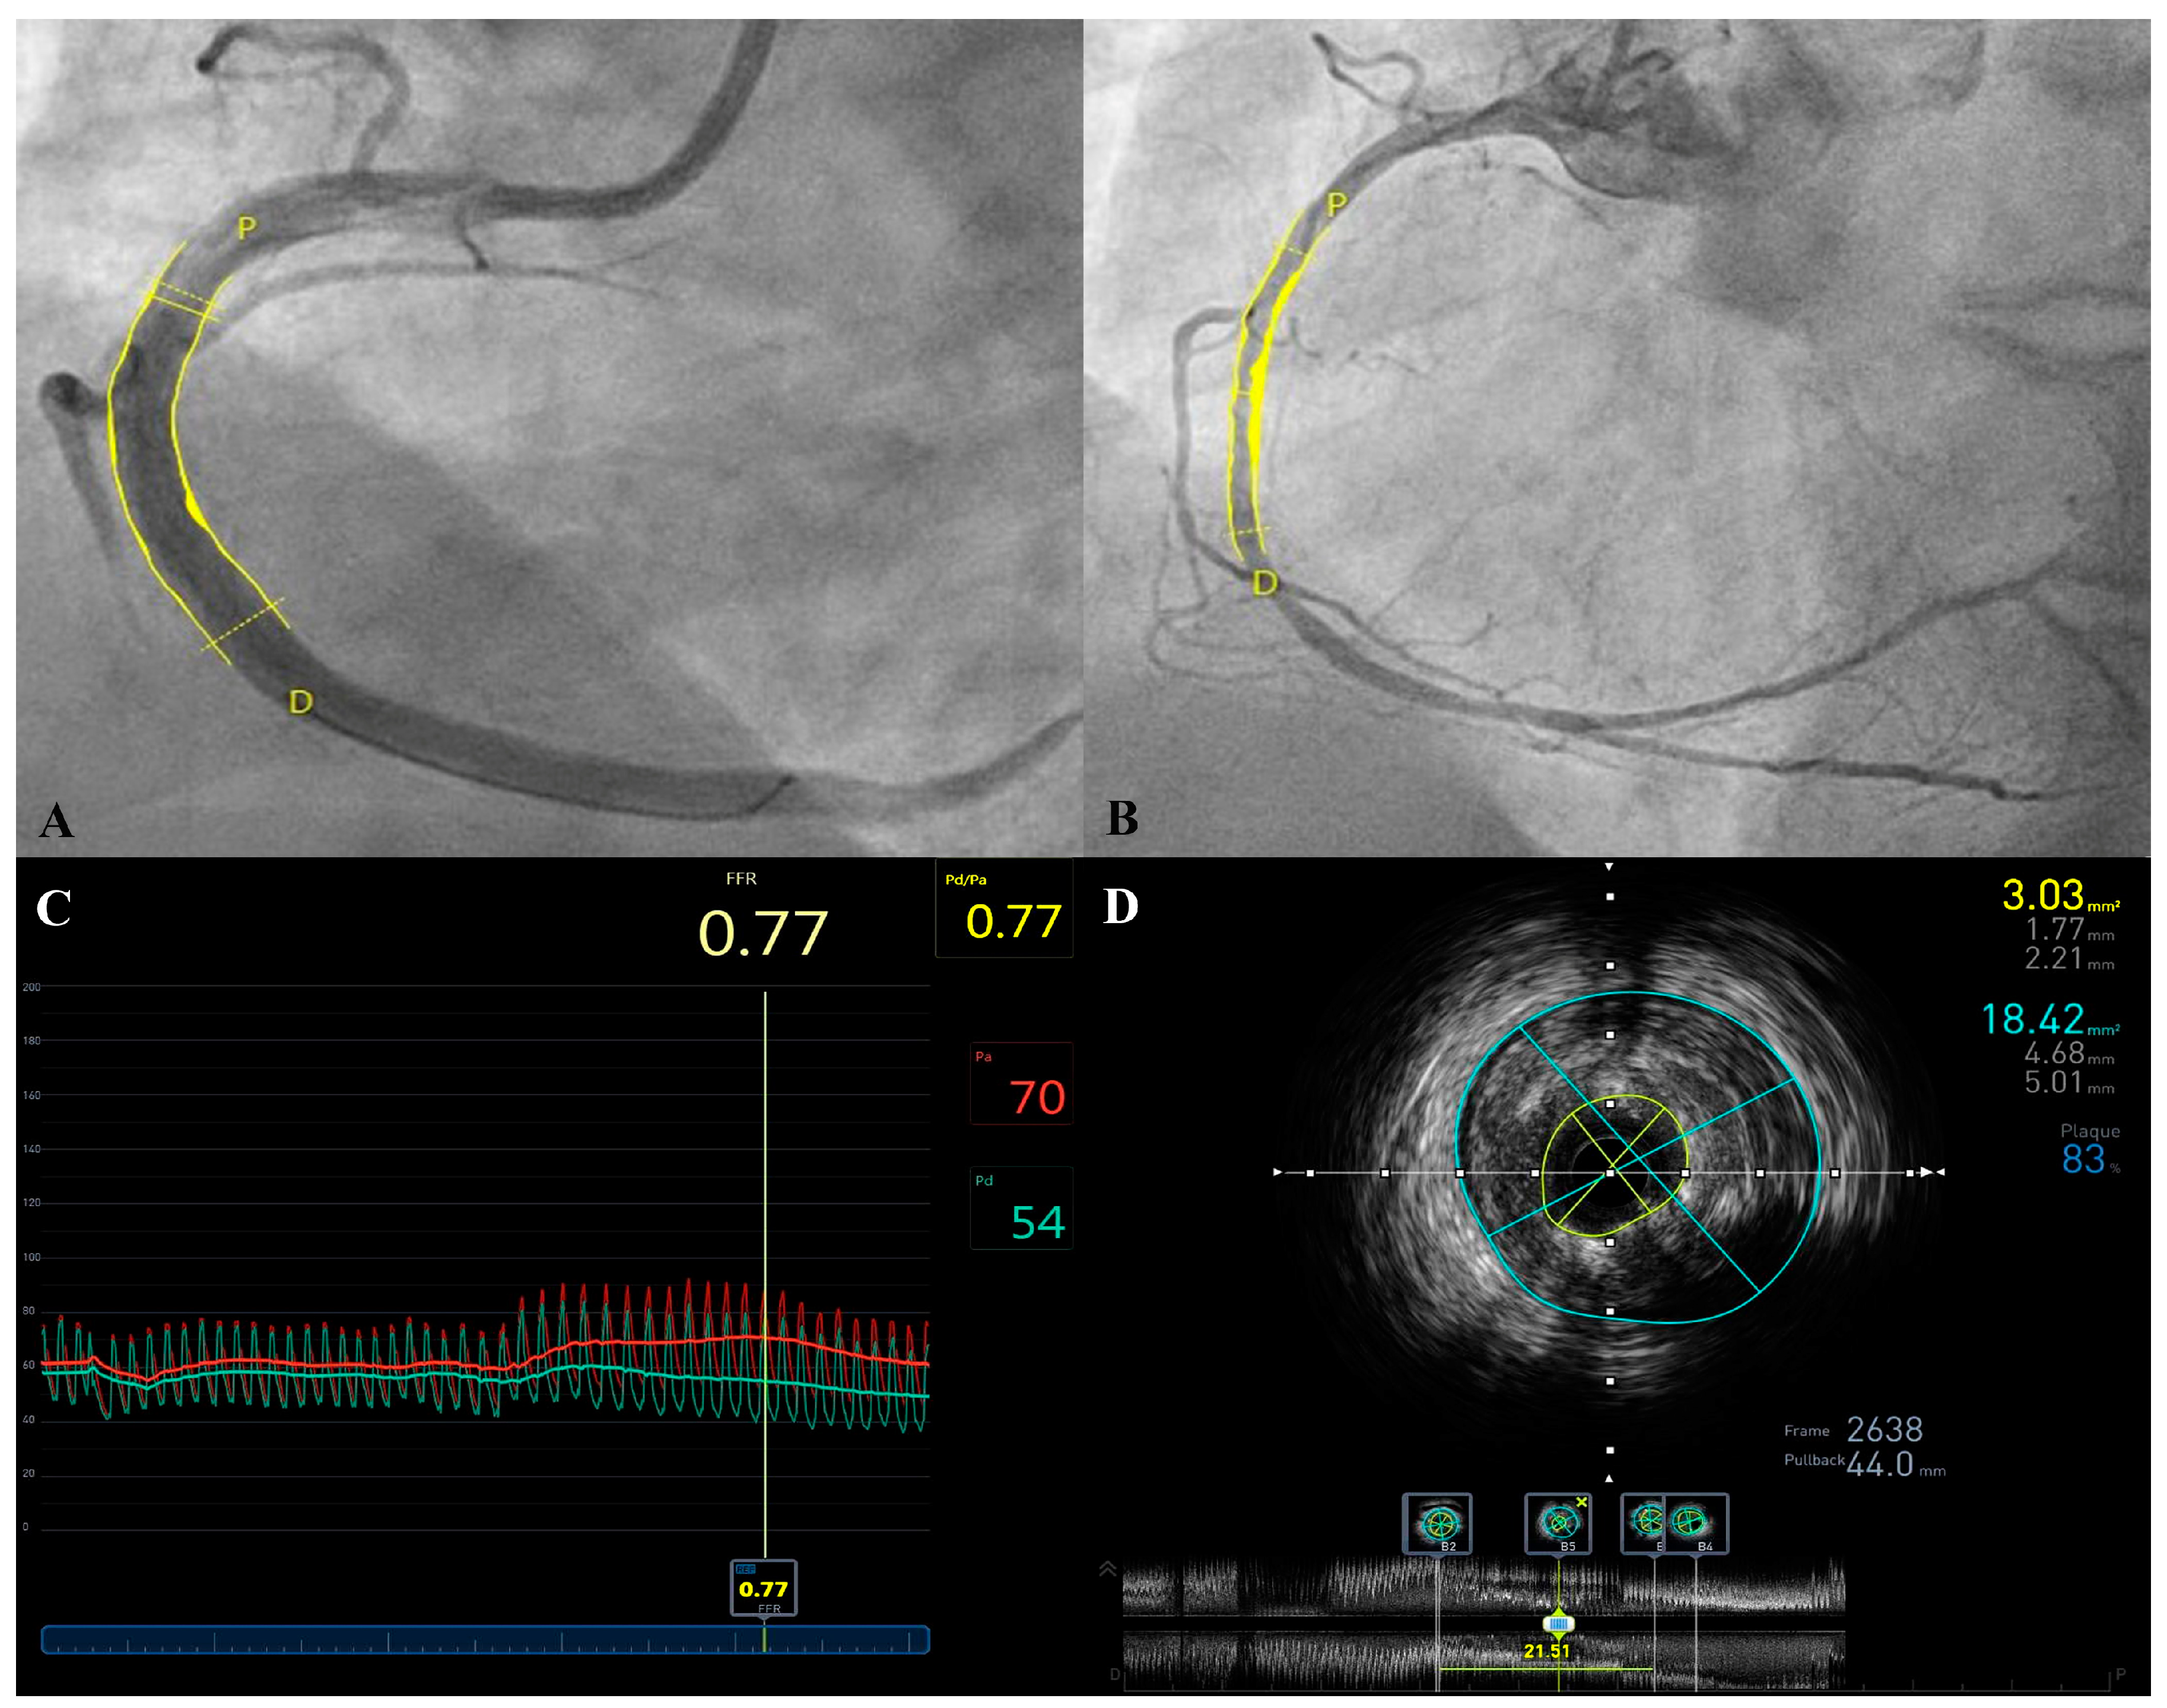

| n | 15 | 17 | 32 | |

| Date difference (months) | 7.1 ± 4.5 | 5.6 ± 2.5 | 6.4 ± 3.7 | NS |

| Proximal vessel diameter (mm) | 4.0 ± 0.3 | 3.8 ± 0.7 | 3.9 ± 0.5 | NS |

| Distal vessel diameter (mm) | 3.3 ± 0.6 | 3.1 ± 0.6 | 3.2 ± 0.6 | NS |

| Proximal surface area (mm2) | 9.4 ± 1.9 | 10.0 ± 3.7 | 9.7 ± 2.9 | NS |

| Distal surface area (mm2) | 7.4 ± 2.1 | 7.1 ± 2.9 | 7.2 ± 2.5 | NS |

| In-stent minimal diameter (mm) | 2.4 ± 0.4 | 2.4 ± 0.7 | 2.4 ± 0.6 | NS |

| In-stent maximal diameter (mm) | 4.1 ± 0.5 | 3.9 ± 0.9 | 4.0 ± 0.8 | NS |

| Minimal in-stent surface area (MSA) (mm2) | 6.1 ± 1.2 | 6.8 ± 2.6 | 6.5 ± 2.0 | NS |

| Maximal in-stent surface area (mm2) | 11.3 ± 2.5 | 10.9 ± 3.4 | 11.1 ± 3.0 | NS |

| Mean proximal to distal surface area (mm2) | 8.4 ± 1.6 | 8.5 ± 2.9 | 8.4 ± 2.3 | NS |